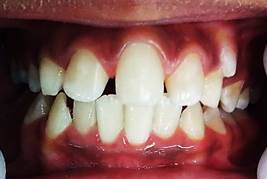

Phase 1 started on 8 June 2021, and the patient was scheduled for monthly checkups for six months. In December 2021, a photographic control was performed, showing a decrease in the overjet and overbite, an improved profile, and a corrected deep bite (Figures 5 and 6). The patient attended checkups until the first year of treatment.

Figure 5: After six months of treatment, the frontal photograph shows an improved deep bite; the central incisor remains in the midline

Figure 6: Lateral photograph after six months of treatment showing correction of mandibular retrognathism